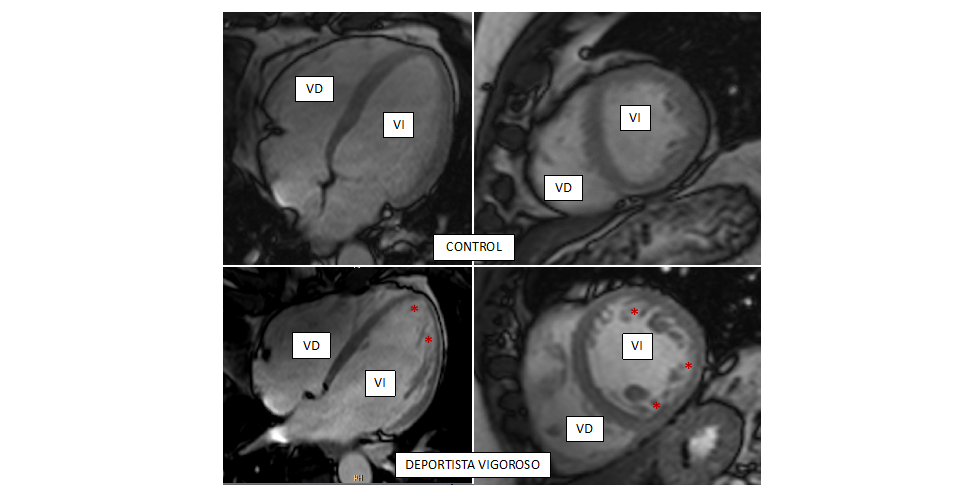

• CIBERCV

Ejercicio vigoroso, corazón esponjoso

06/10/2020